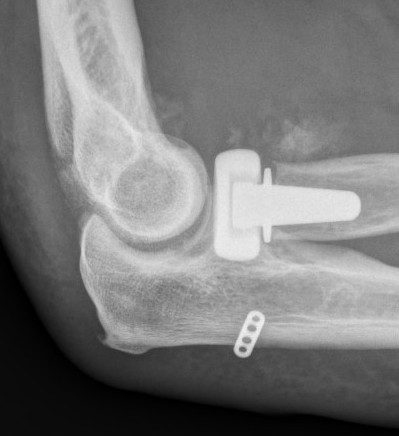

rh orif Radial Head Replacement Lateral

Radial head replacement

+ LCL repair / reconstruction

+/- MCL repair / reconstruction if unstable

Radial head replacement with lag screw fixation of Type II coronoid

terribleterribleterribleterrible

Radial head replacement with lasso fixation of small coronoid fragment